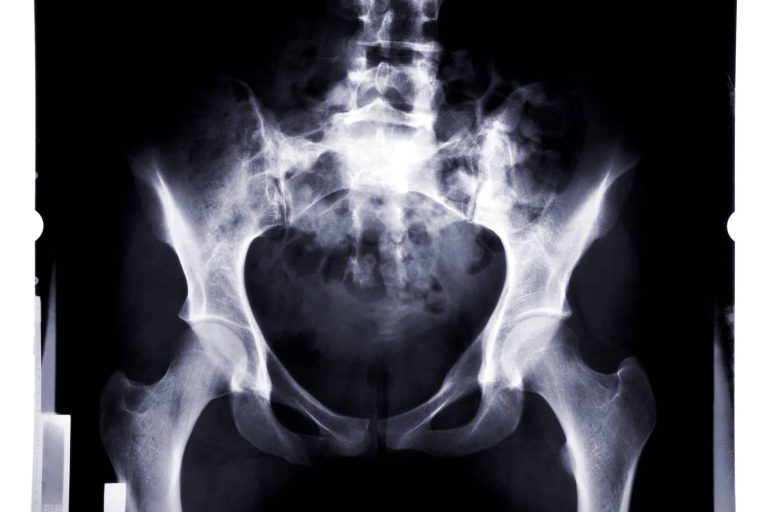

Vitamin D Versorgung im Sport – verbessert Muskelfunktion, verringert Risiko von Knochenbrüchen

Der weit verbreitete Vitamin-D-Mangel unter Sportlern erhöht das Verletzungsrisiko erheblich. Das ist das Ergebnis einer US-Studie. Sportler ernähren sich in der Regel bewusster sowie gesünder als andere Menschen. Sie bewegen sich mehr und sind häufiger an der frischen Luft. Eigentlich sollte es bei ihnen also keine Probleme mit der Nährstoffversorgung geben. Leider scheint dies jedoch…